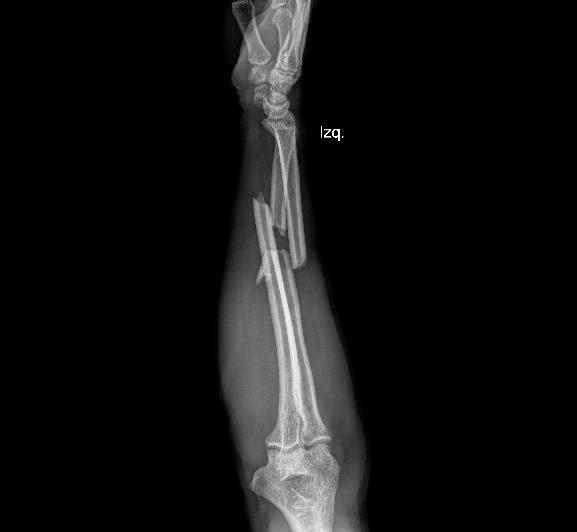

OSTEOSÍNTESIS

Paciente en postoperatorio de osteosíntesis de radio distal, que al inicio de la terapia presentaba marcada rigidez articular y limitación funcional. El proceso de rehabilitación convencional ha sido limitado, con solo dos sesiones de fisioterapia realizadas por EPS.

Las imágenes corresponden a la evolución a los dos meses de seguimiento, donde se documenta el estado funcional actual y los cambios observados pese a la baja frecuencia de terapia convencional.